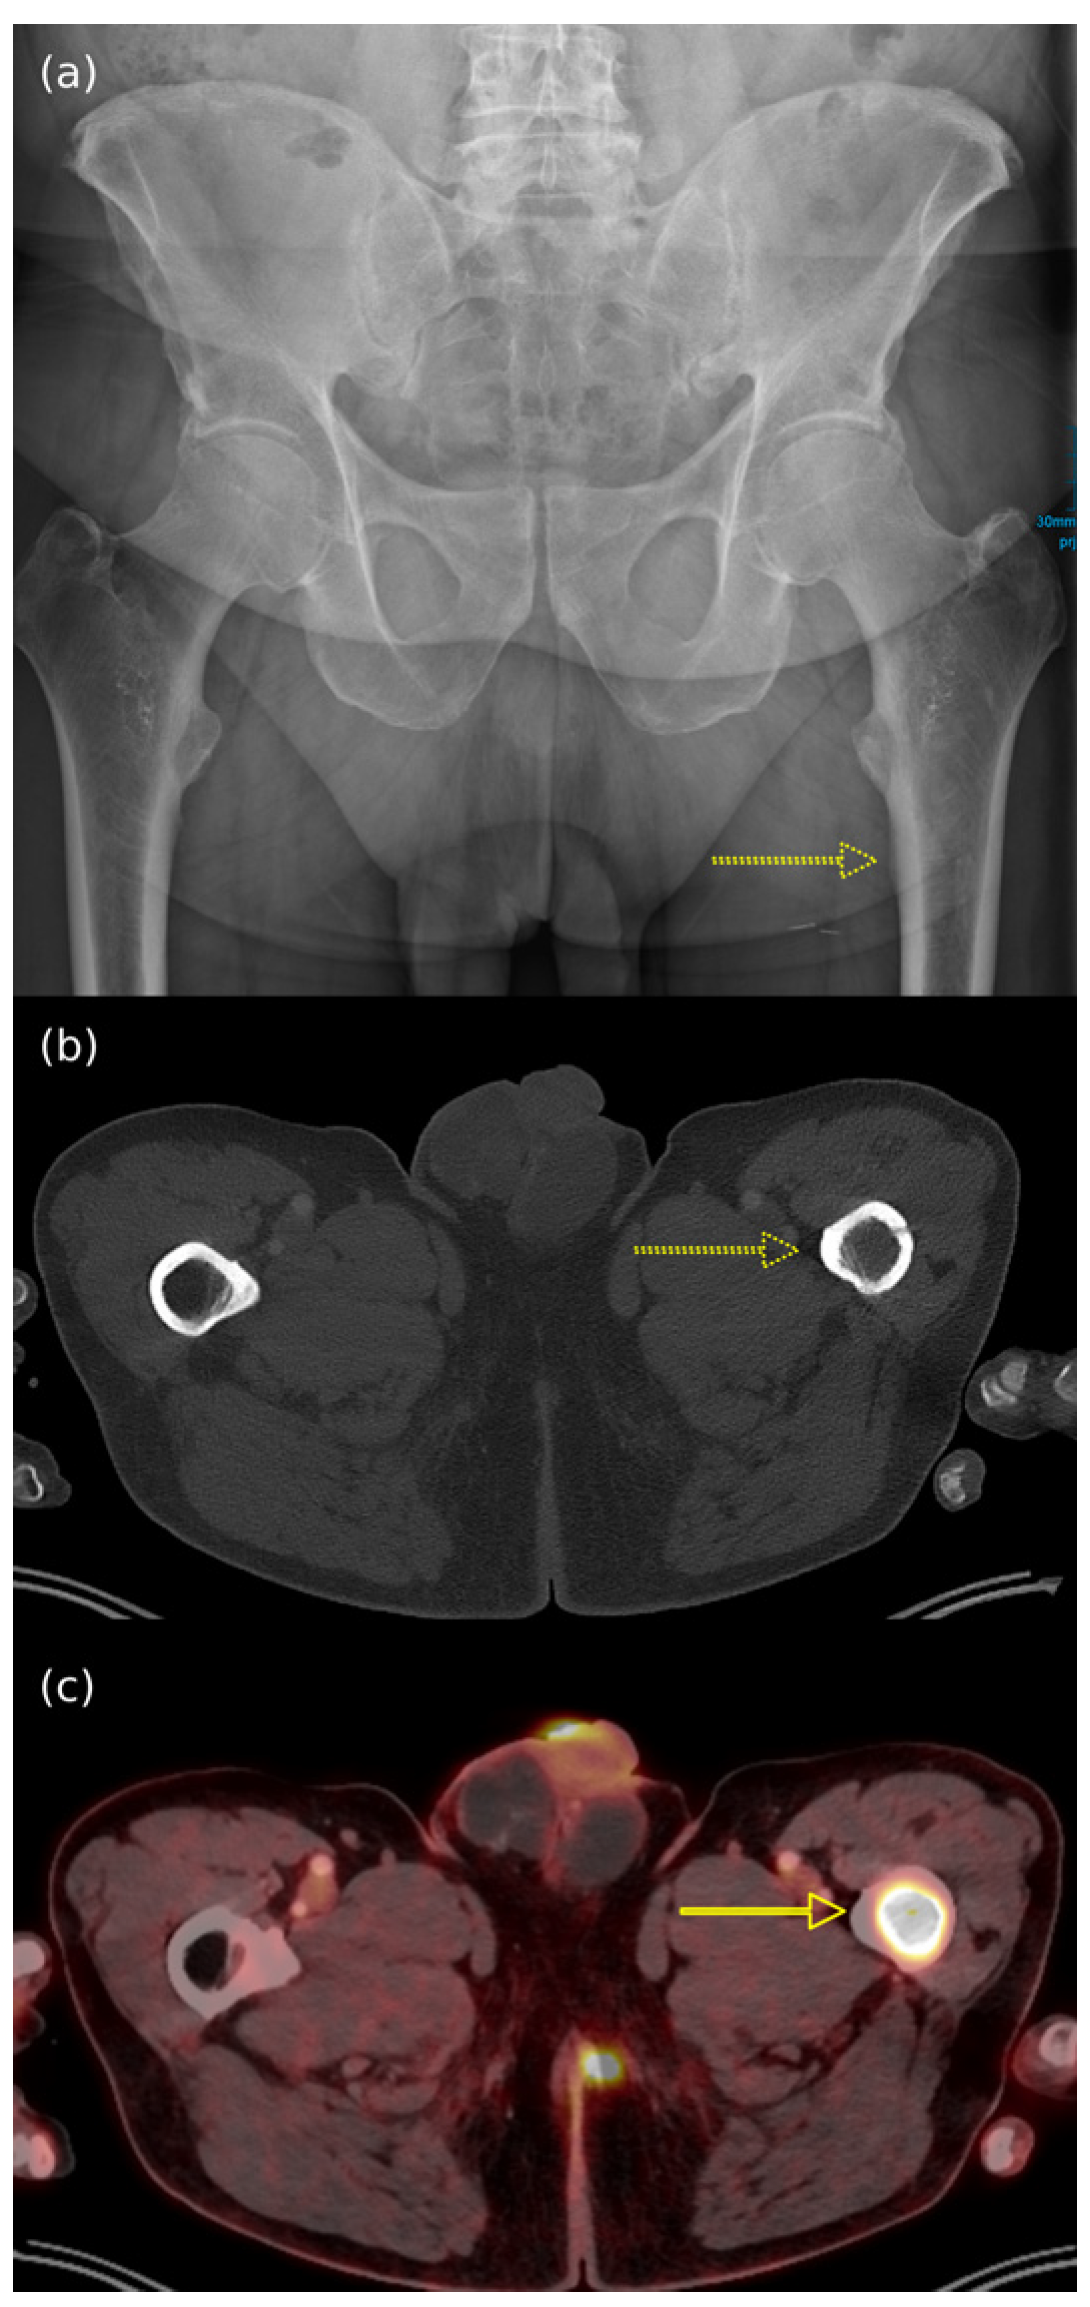

- Oh, H.Y.; Kim, D.; Choi, Y.S.; Kim, E.K.; Kim, T.E. Merkel Cell Carcinoma of the Trunk: Two Case Reports and Imaging Review. J. Korean Soc. Radiol. 2023, 84, 1134–1139. [Google Scholar] [CrossRef]